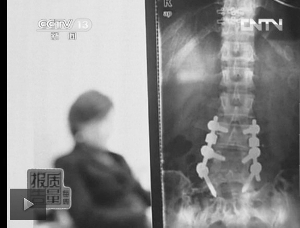

图1:教练按压导致学员腰椎间盘突出。(央视截屏)

瑜伽练习导致损伤的事件,近些年时常被媒体报道,并非偶然。2011年,湖北有位女性因瑜伽指导不当,造成大腿严重骨折,瑜伽场所最终需赔偿损失;2010年,上海郑某在瑜伽过程中,受指导人员过度按压,引发腰椎间盘问题,现今其第4、5节腰椎已植入四颗金属固定钉(图1)。